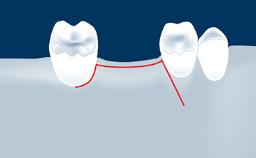

• intraoperative complications of lateral window sinus floor elevation

• intraoperative complications of transcrestal sinus floor elevation

• postoperative complications of sinus floor elevation